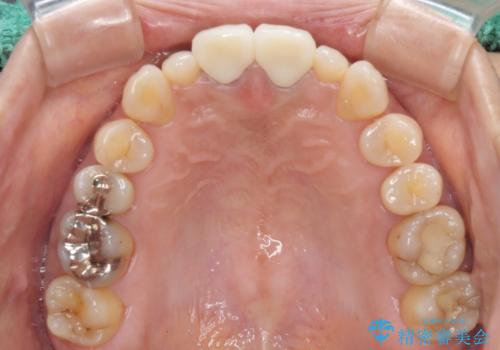

- 他院で奥歯に虫歯があると言われて、ご来院された患者様です。チェックしたところ、奥歯に虫歯は認められませんでした。

前歯に違和感や根尖病巣(根の先に細菌が溜まっている)が認められたため、治療をご提案しました。

セラミック治療と根管治療を行いました。

患者様は、もともと奥歯の虫歯を心配してご来院されましたが、前歯に問題が見つかりました。

金属を使用したメタルボンドクラウンが入っていたため、いつかオールセラミックにしたいときに根管治療も行ったほうが良いとご提案し、今回行いました。

色について

歯と歯肉の境目の色は、歯自体が黒くなっている場合、完全にカバーすることは難しいです。